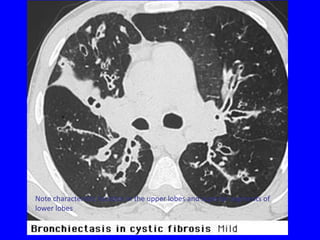

Characteristic central bronchiectasis 2/2 ABPA

Note characteristic location in the upper lobes and superior segments of

lower lobes